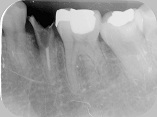

エックス線写真  |

近心から遠心にかけて  |

垂直に破折し分離  |

接着剤を塗って復元  |